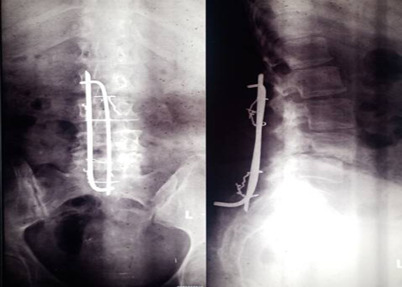

Background: Due to resource constraints, advanced spinal stabilization methods such as pedicle screws are unavailable at our center. Adeolu's technique, which employs low-cost and readily available vertical struts and spinal process wires, has been used as an adjunct in treating various spinal conditions to achieve rigid spinal constructs. This study evaluates the long-term clinical outcomes of this technique.

Methods: Nineteen patients treated with Adeolu's technique were prospectively followed to assess clinical outcomes. Primary outcomes included symptom reduction, absence of adverse events or need for re-intervention, and radiological evidence of stabilization and unrestricted mobilization. Secondary outcomes included back pain intensity, implant-related complications (rotation, migration, back-out, fracture), wound infection, worsening neurological status, and need for implant removal Data were analyzed using SPSS with simple descriptive statistics.

Results: The average follow-up period was 4.1 years (Range: 0.1 - 9.0 years). Patients' ages ranged from 20 to 81 years (Mean: 48.5). Indications for surgery included lumbar spondylosis (7, 36.8%), spinal trauma with unstable fractures (4, 21.1%), spinal tumors (4, 21.1%), and Pott's disease (4, 21.1%). All patients achieved satisfactory primary outcomes. Implant rotation was observed in 4 patients (21.1%), and implant migration in 1 patient (5.3%), requiring removal. Superficial surgical site infection occurred in 2 patients (10.5%). No implant fractures, deep infections, or worsening neurological status were noted.

Conclusion: Adeolu's technique is effective for a range of spinal pathologies, with favorable long-term clinical outcomes.